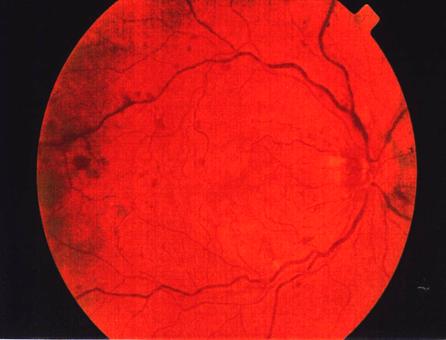

Fig.

2

OVCR - forma ischemica